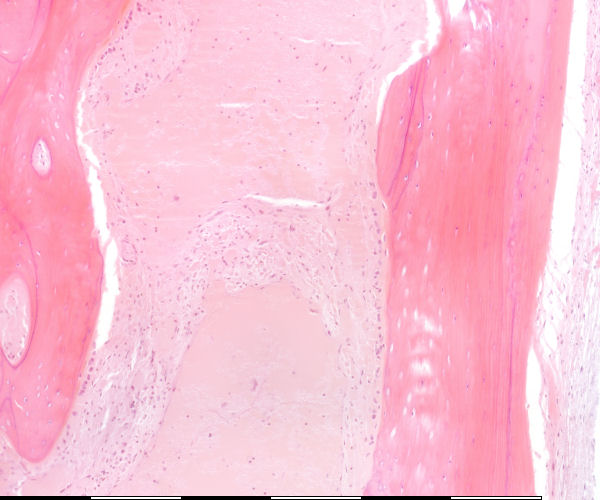

Medium magnification of immature bone

Osteosiete / Osteocytes Lakunae / Lacunae Groeilyne / Growth reversal lines Aktiewe periosteum / Active periosteum Losmasige bindweefsel / Loose connective tissue Osteoblaste / Osteoblasts Laag van osteoblaste / Layer of osteoblasts Lamellêre laag kortikale been / Lamellar layer of cortical bone